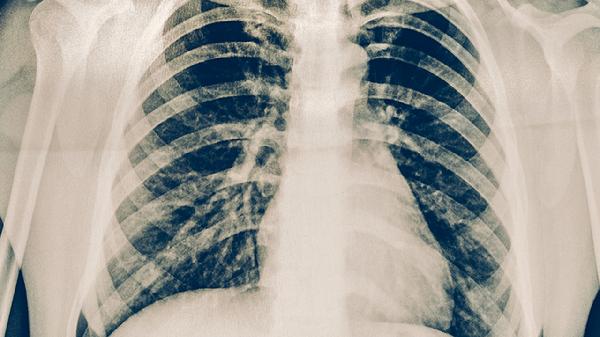

肺结核的饮食原则是什么

肺结核患者需遵循高蛋白、高热量、高维生素的饮食原则,同时保证营养均衡和易消化吸收。主要原则包括增加优质蛋白摄入、补充足量维生素、适量增加热量、避免刺激性食物、保持水分充足。